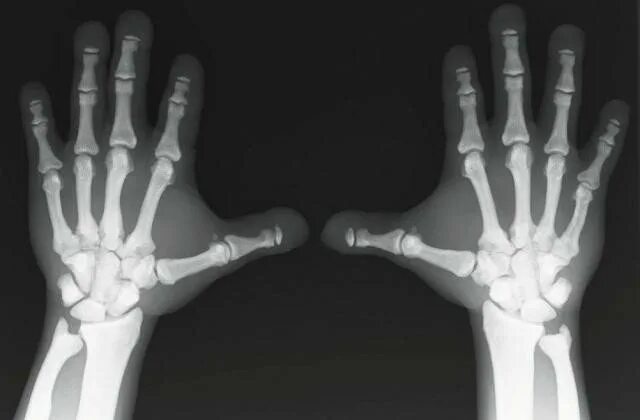

Что такое остеосклероз